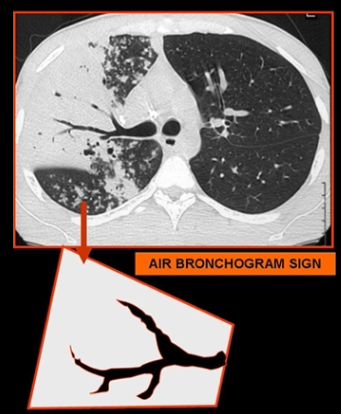

Broncograma aéreo

Indicador de ocupación alveolar

Dato clve de patrón de ocupacion alveolar

Radioopaco/Hiperdenso con broncograma aéreo (bronquios llenos de aire)